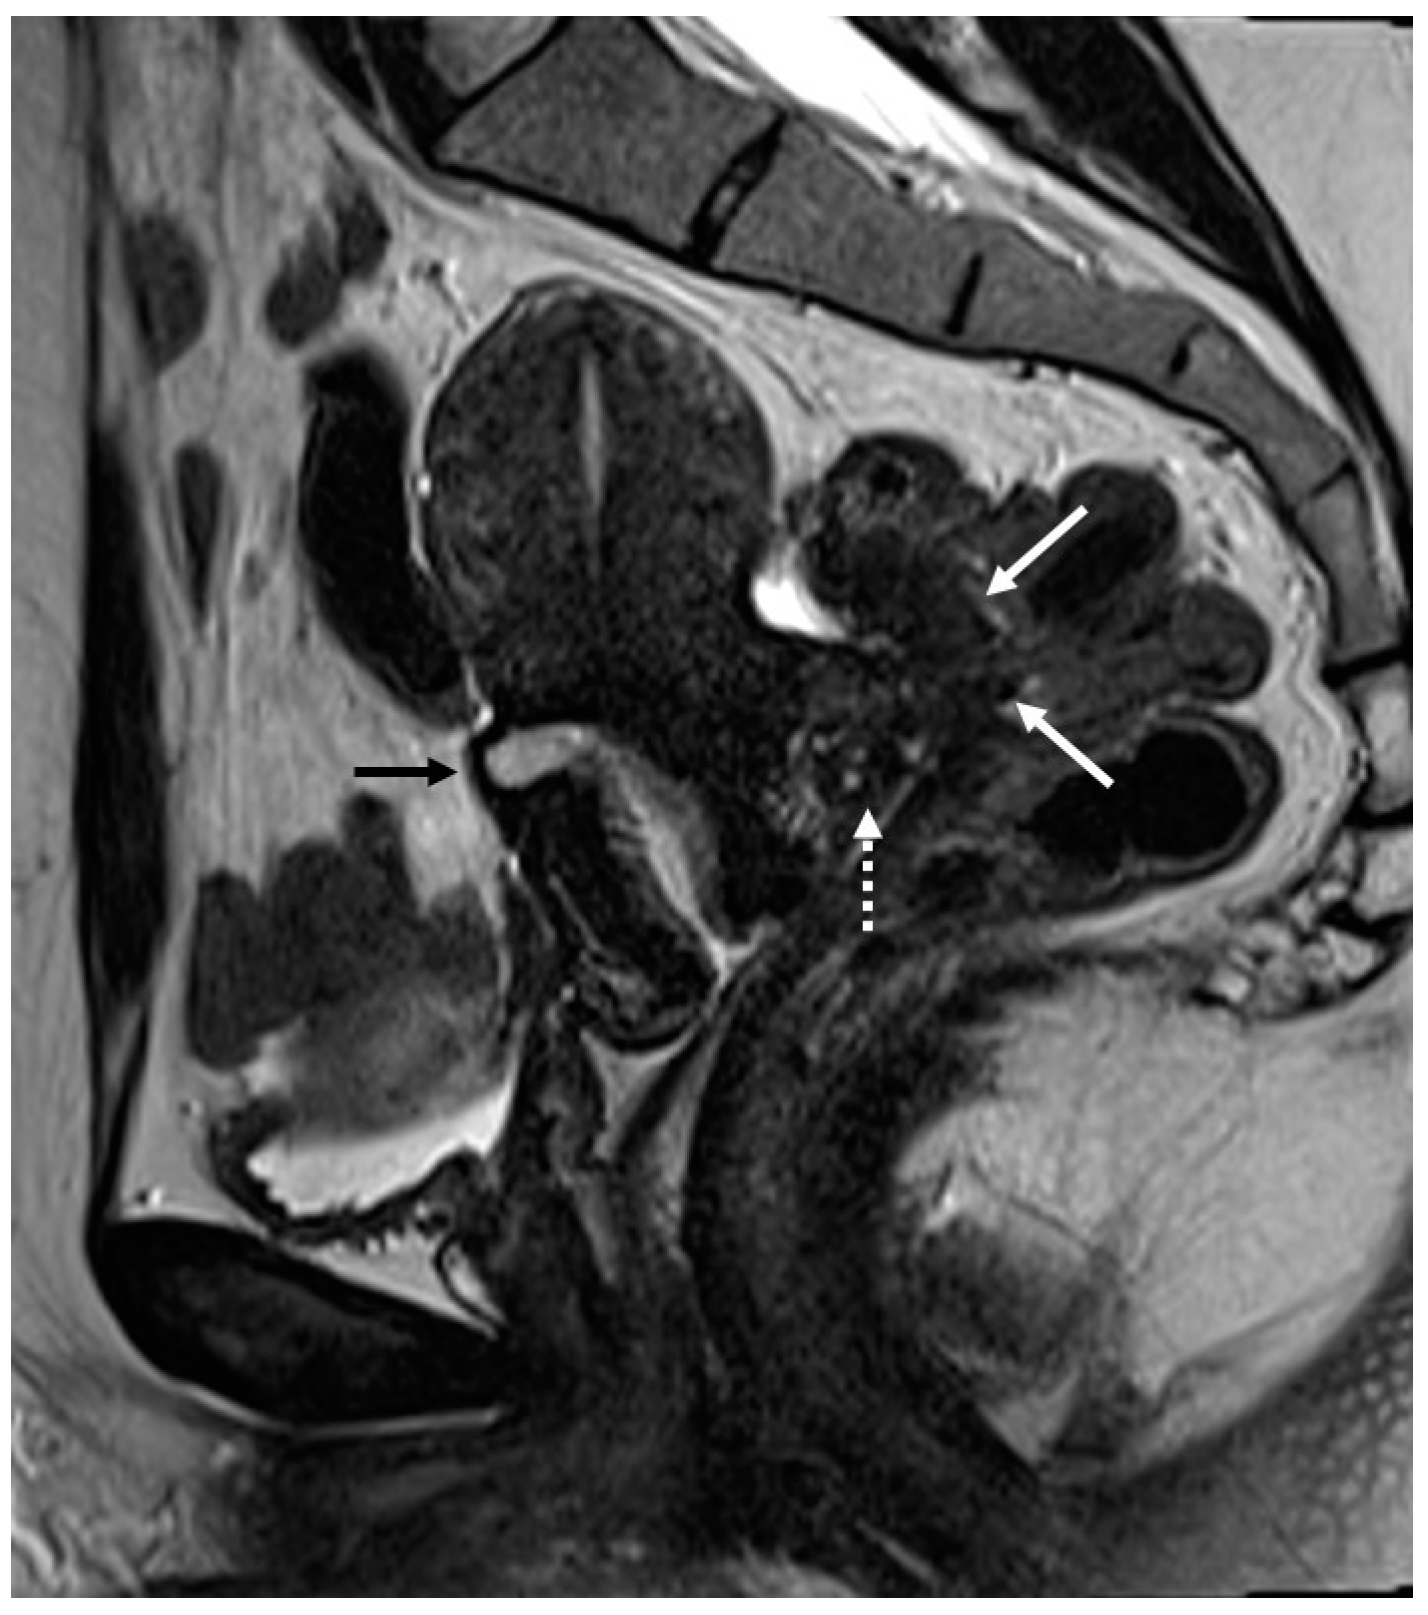

Figure 2.

Deep infiltrating endometriosis of the anterior and posterior compartments in 33-year-old female with dysmenorrhea, chronic pelvic pain, dyspareunia and dyschezia. (A) Sagittal T2WI. Evidence of external anterior adenomyosis and plaque of the vesico-uterine pouch (white arrow); (B) Sagittal T2WI. Retrocervical localization of DIE (white arrow); (C) Axial T2WI. Left uterosacral ligament (USL) localization (white arrowhead), plaque of vesico-uterine pouch (white arrow) with involvement of the round ligaments, particularly on the left (white dotted arrows), and adhesions with the ovaries (retraction of the broad ligaments).

Involvement of the proximal portion of ligaments (distance less than 2 cm from the cervix) may, in some cases, be associated with thickening at the level of the torus uterinus; in such cases, it is essential to report any mass or thickening in the upper portion of the posterior cervix, as this could cause the surgeon to proceed with a laparoscopic trans-vaginal approach [7] (Figure 2, Figure 3 and Figure 4).

Figure 3.

Right uterosacral ligament localization in a 43-year-old female. The right uterosacral ligament appears thickened at uterine insertion (white arrow).

Figure 4.

Retrocervical endometriosis plaque, intestinal localization, kissing ovaries with bilateral ovarian endometriomas. (A,B) Axial T2WI; (C) Coronal T2WI. Hypointense retrocervical plaque (white arrowhead in (A)) localized in the uterine torus with involvement of the utero-sacral ligaments. Adhesions involve both ovaries with bilateral endometriomas (white arrows), which are prolapsed in a retro-uterine position and adhered to the utero-sacral ligaments and the recto-sigmoid junction. There is also an eccentric anterior parietal thickening in the recto-sigmoid junction suggestive of intestinal endometriosis lesion (white dotted arrow in (A)).